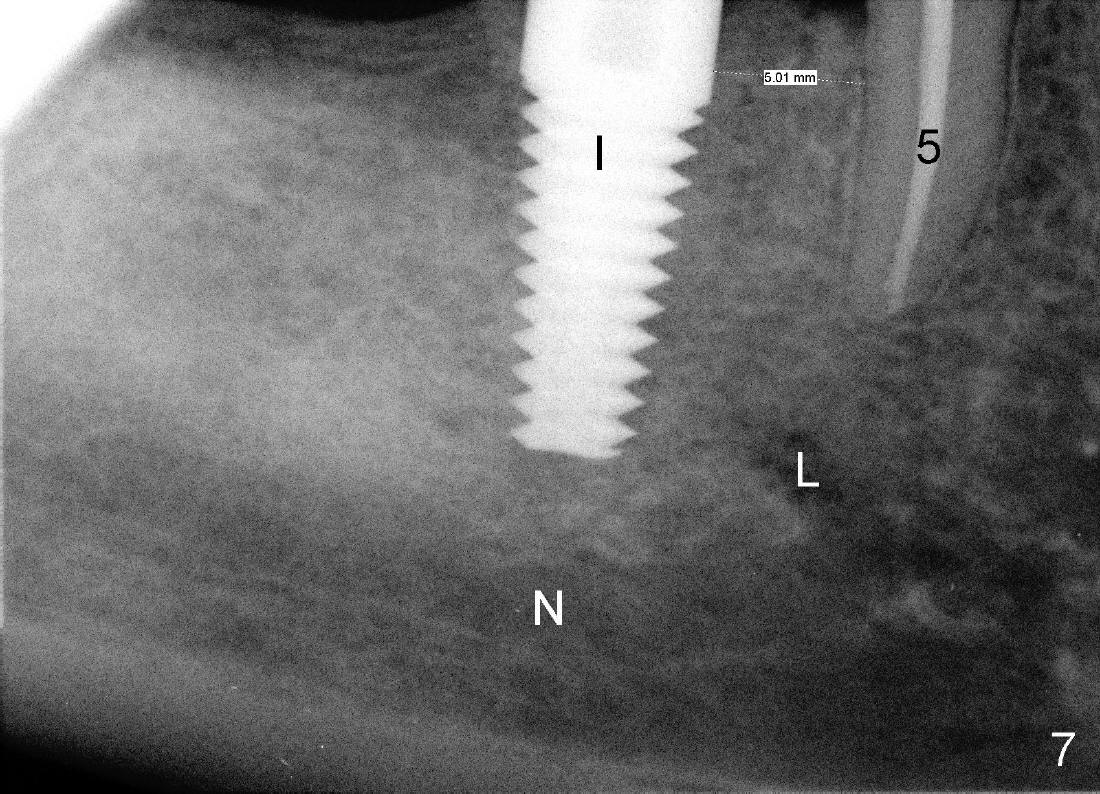

陈先生五十来岁,牙齿不好,右上有一个三个单位桥(图一:5-7),右下四个单位桥(5-8)。五年前他第一次来诊所时左上7有牙髓炎症状(图二),那颗牙齿有很大银汞充填物(A),之下出现龋齿(*)。出于救死护伤精神,开始做根管治疗(图三:*牙胶尖),当时他原来牙医出差了,之后给左上7戴上牙冠(图四:C)。其实图四X光片拍摄是在左上7根管治疗之后一年半,这次左上5有牙髓炎症状,再次为他做根管治疗(图五:*)。他又很久才回来:两年半,这次问题更严重:左上7断了(图五),好在他毫无怨言,可能与他是修理工有关,牙齿也需要修修补补。他也知道现在必须做植牙,这时我们非常自豪告诉他我们能做植牙,他便回家凑钱。一年半后他又从天降,左上问题还没有解决,右下8基牙在桥下出现龋齿(图六:^),必须拔除,这时右下6,7必须先做植牙(图六:植牙设计;N:下齿槽神经; L:颏神经襻(loop))。末端缺牙做活动义齿效果不好,据研究表明它只能恢复百分之十咀嚼功能,而植牙百分之百。

首先,在右下六号牙处植牙(图七:I),没有伤及下齿槽神经(N)或者颏神经襻(L)。回学术讨论园地